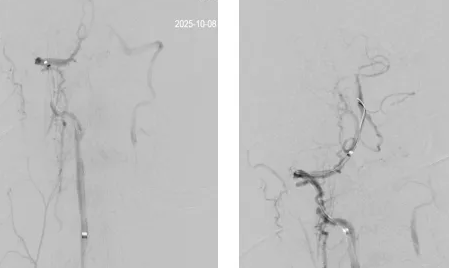

席聪准确锁定患者基底动脉处血栓,采用抽吸取栓技术快速开通血管,成功取出堵塞部位2cm的血栓。再次造影示:右侧大脑后及双侧小脑上动脉再通,右侧大脑后动脉P3段以远闭塞,考虑慢性闭塞,推注替罗非班,血流明显加快。随后采用支架植入术开通右侧椎动脉开口处,术中影像显示:支架贴壁良好,无明显残余狭窄,颅内血管显影良好。

术后,患者症状明显好转,神志清楚,右手无力、视物模糊症状明显改善,术后24 小时可下床活动,NIHSS评分1分,mRS评分2分。